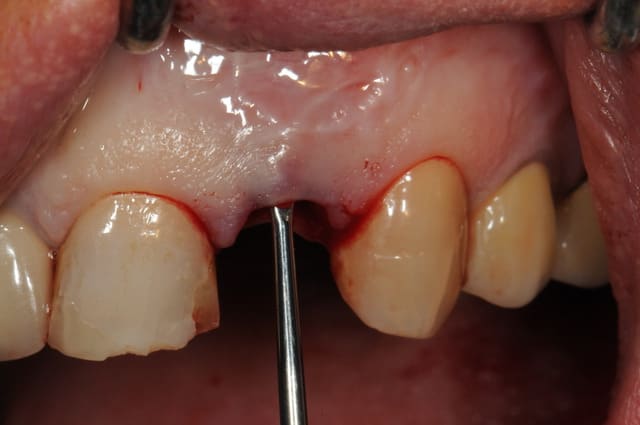

Le cas EII sur 12

positionnement de l'implant en ménageant un espace en vestibulaire qui st comblé avec de l'os synthétique car l'espace est important et il y a une perforation de la corticale vestibulaire en regard de l'apex de la dent.

pour recouvrir tout cela et gagner un peu de volume vestibulaire

un lambeau palatin pédiculé qui après une rotation va recouvrir l'implant et la greffe.